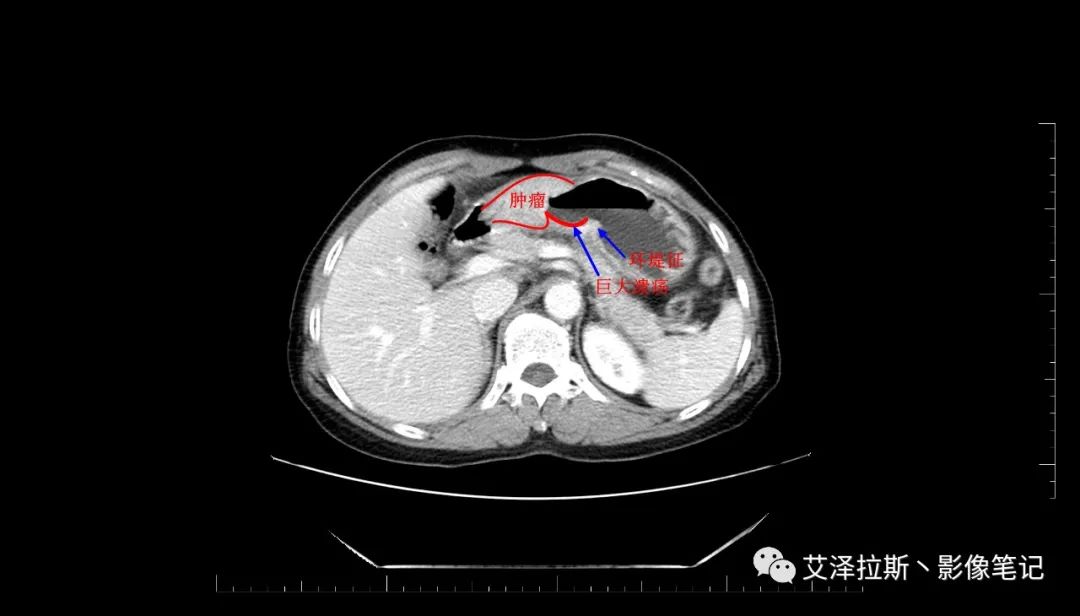

【影像所見】 胃竇部狹窄,胃壁環形增厚,小彎側見一巨大潰瘍,周圍伴“環堤征”,漿膜面不完整,胃周脂肪見網格狀條索影,病灶與肝臟左葉、胰腺鉤突脂肪間隙消失,增強掃描病灶明顯強化。引流區內約15個區域淋巴結受累。

【診斷意見】 胃竇部胃癌(T4N3期) 該病例腫塊突破漿膜層,與肝臟左葉、胰腺鉤突分界不清,脂肪界面消失,定為T4期; 受累及的淋巴結為15個區域,定為N3; 有無遠處轉移尚不明確,所以M期暫時無法確定。